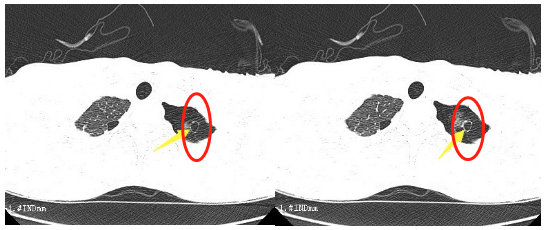

這段時(shí)間,16歲的小王突然出現(xiàn)了胸悶的癥狀,持續(xù)一周都不見好轉(zhuǎn)。到我院胸心外科檢查后,胸片提示左側(cè)液氣胸,積氣為主,結(jié)合患者術(shù)前CT檢查情況,考慮為肺大泡破裂引起的氣胸。

“肺大泡,也叫肺大皰,是指由于各種原因?qū)е路闻萸粌?nèi)壓力升高,肺泡壁破裂,互相融合,在肺組織形成的含氣囊腔。”胸心外科醫(yī)生鄧意平說,肺大泡的增大或增多,會(huì)使肺功能發(fā)生障礙并逐漸出現(xiàn)癥狀,像小王這樣年紀(jì)輕輕的小伙子也可能出現(xiàn)胸悶、氣短等癥狀。